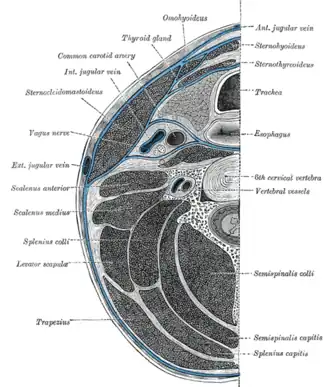

Section of the neck at about the level of the sixth cervical vertebra. Showing the arrangement of the deep cervical fascia | |